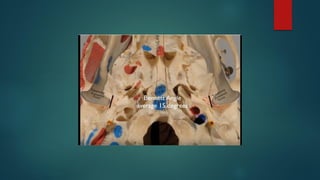

Placement of Reference Lines on the Maxillary and Mandibular Units (see

Fig. 13-5, A through E)

• With the use of the Erickson Model Table, “score” two horizontal reference lines on the

maxillary unit and then on the mandibular unit. Locate the horizontal reference lines on

the maxillary and the mandibular units by doing the following:

• Place the first horizontal line within the green stone.

• Place the second horizontal line within the white plaster.

• Ideally, there will be 15 mm to 20 mm of separation between these lines.

• With the use of a thick, black Sharpie pen, mark the “scored” horizontal

circumferential reference lines on both the maxillary and mandibular units.

• With the use of a thick, black Sharpie pen, mark the vertical reference

lines on both the maxillary and mandibular units. The vertical lines are

located perpendicular to the horizontal lines and in the following places:

• At the cusp tip of each canine (2 lines)

• At the mesiobuccal groove of each first molar (2 lines)

• Between the central incisors (i.e., at the dental midline) (1 line)

• Posterior at each tuberosity or retromolar area (4 lines)